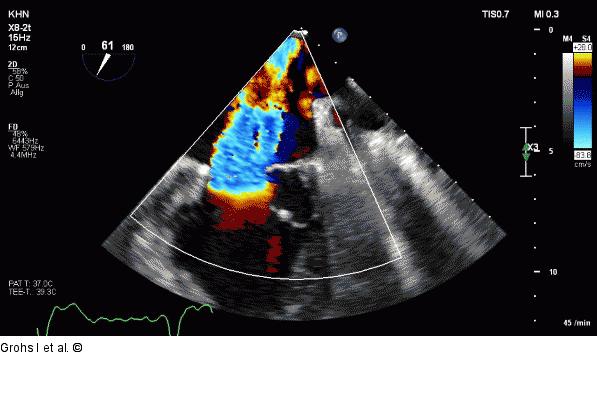

Abbildung 7: Echo-Bild Online 7 CAVE: elliptische PISA - ERO, RV werden unterschätzt |

Abbildung 7: Echo-Bild Online 7

CAVE: elliptische PISA - ERO, RV werden unterschätzt |